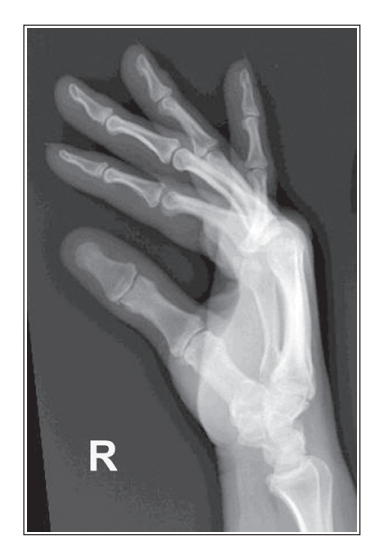

What’s wrong with this oblique finger?

More than 45 degrees obliquity

Over-rotation